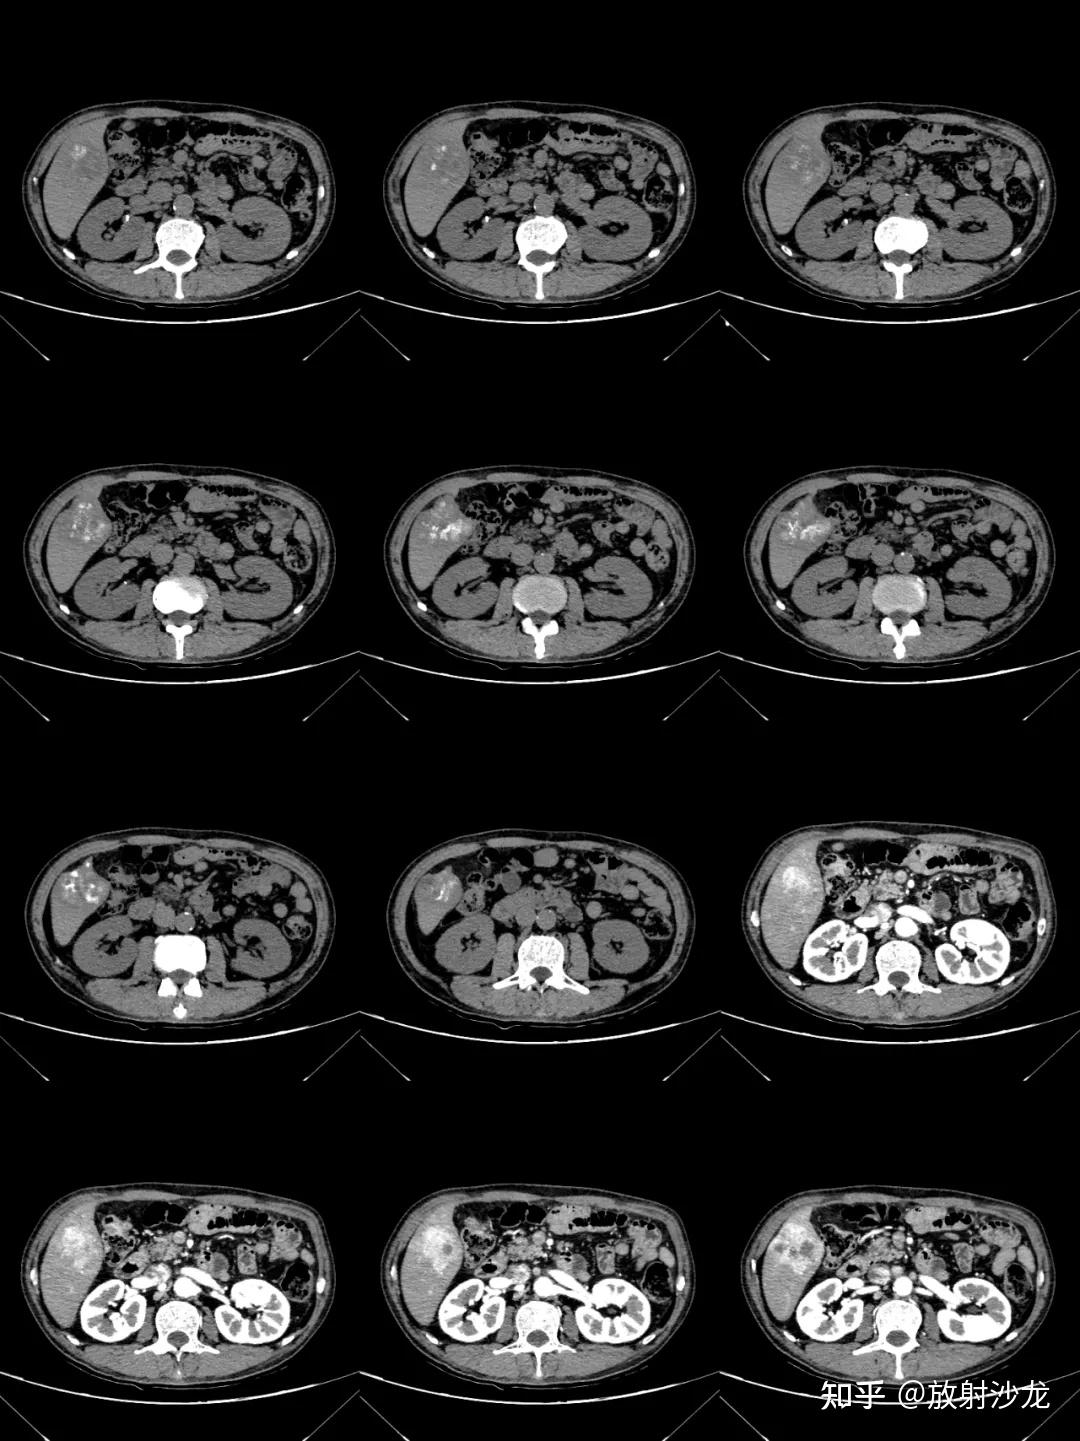

【讨论】肝脏钙化ct [病例帖]